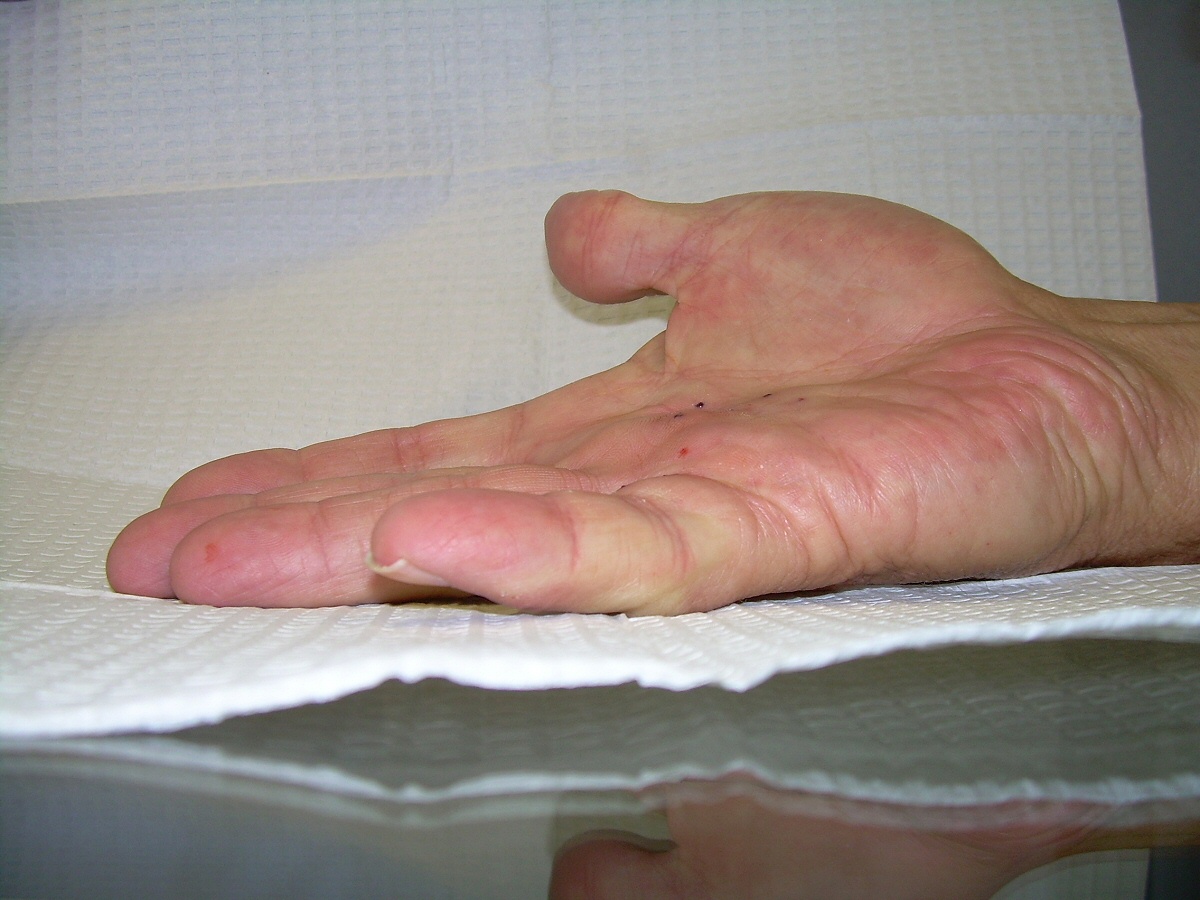

Case 4.

57 year old right handed man with a 22 year

history of Dupuytren disease affecting his

left small finger.

Highslide Highslide

Planning of portals (dots) and nodule steroid

injection sites (circles).

Radiograph of affected finger, 90° contracture.

End of Procedure. Minimal improvement, but the

joint felt rubbery to passive stretch, and so he

was treated with a night time static extension

splint. He had progressive improvement.